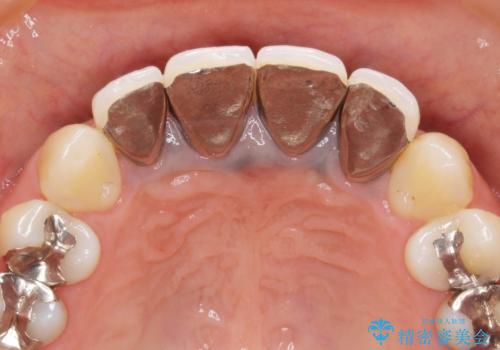

金属を用いたコア・クラウンが装着されており、全ての金属を除去したのちのメタルフリー治療を計画します。

ファイバーコア・セラミッククラウンは金属を用いない審美的な治療法です。